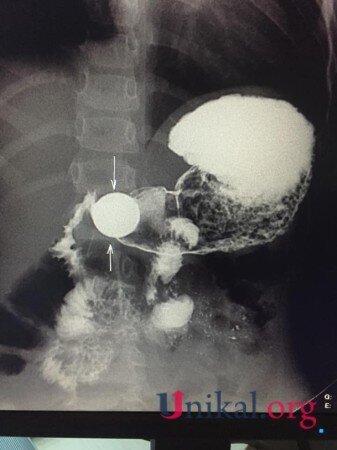

“Bir həftə qabaq 4 yaşında uşaq 5 qəpik udub. Bir həftədir qəpik uşağın mədəsindən ifraz olunmur. Gətiriblər müayinəyə, biz də aşkar etdik ki, qəpik hələ mədədir. Mədənin çıxacaq hissəsi uşaqlarda dar olduğuna görə çıxmır. Qəpiyin diametri mədənin çıxacaq hissəsinin diametrindən iki dəfədən çox böyükdür. Ona görə mədədən keçmədi, qalıb mədədə. Biz məsləhət gördük ki, endoskopiya müayinəsindən keçsin, endoskopik yolla çıxartsınlar. Hələ bir xəbər yoxdur. Qəpik uşağın mədəsindən çıxarılacaq”.